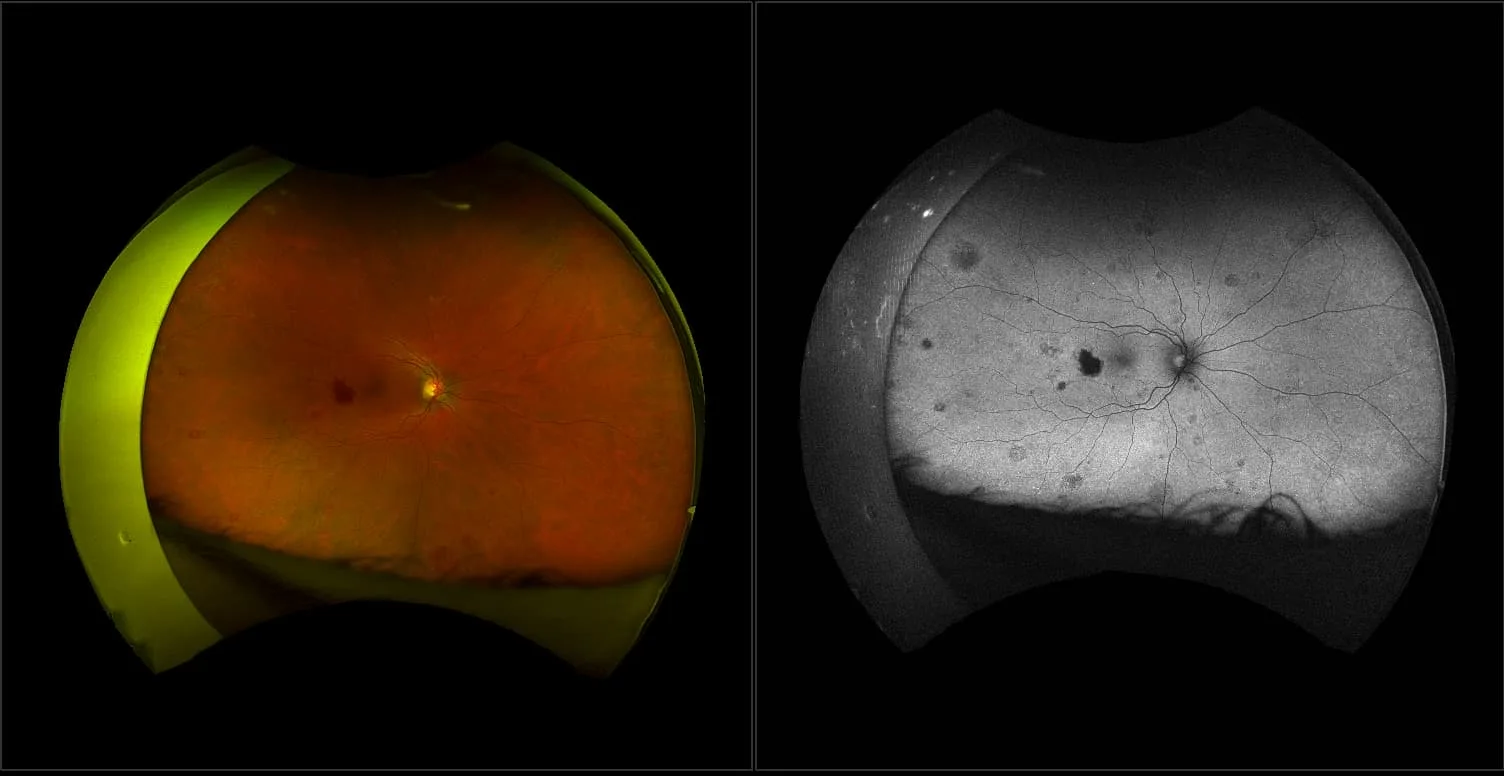

This material is designed as a searchable reference resource to support clinical decision-making. The information contained here should be used as general guidance when viewing optomap and OCT images from Optos devices. The differential diagnosis should be made under the direction of the responsible physician. These images were taken on the latest ultra-widefield optomap devices.

optomap Recognizing Pathology is searchable by pathology and/or optomap image modality. You may search by multiples of each selection. Each individual case is represented by the accompanying thumbnail image. Most cases include several different optomap image modalities. To view a full description of the case, please click on the thumbnail. Each image in the case will be made available through our OptosAdvance software which provides multi-dimensional visualization of digital images to aid in the analysis of anatomy and pathology. Support and pathology definitions can be found by selecting one of the buttons, above. Should you have questions, please complete the form below.